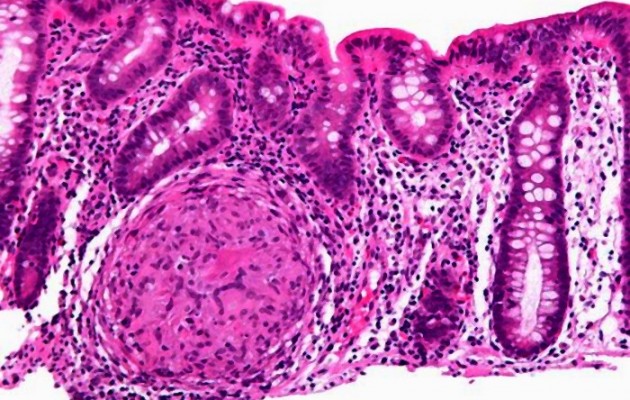

Τα εκκολπώματα είναι τα «σακουλάκια» που δημιουργούνται όταν ο μυϊκός ιστός που στηρίζει το έντερο ατονεί και μέσα από αυτόν προβάλλει τμήμα του εντέρου. Αυτό κυρίως συμβαίνει στα σημεία που τα αιμοφόρα αγγεία εισέρχονται στο έντερο.

Μπορεί να αναπτυχθούν σε όλο το παχύ έντερο, αλλά εντοπίζονται κυρίως στο σιγμοειδές, το οποίο βρίσκεται στην αριστερή πλευρά της κοιλιάς.